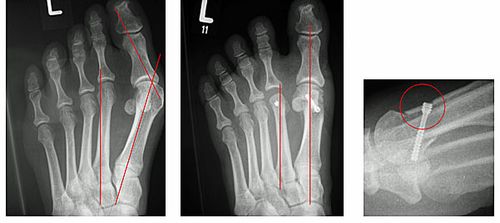

Abb.2: Korrektur einer leichten Hallux valgus Fehlstellung durch eine Chevron Osteotomie (Distale Metatarsale I Osteotomie) mit versenkter Schraube. Der Vorfuß wurde verschmälert und die Knochenachsen begradigt.